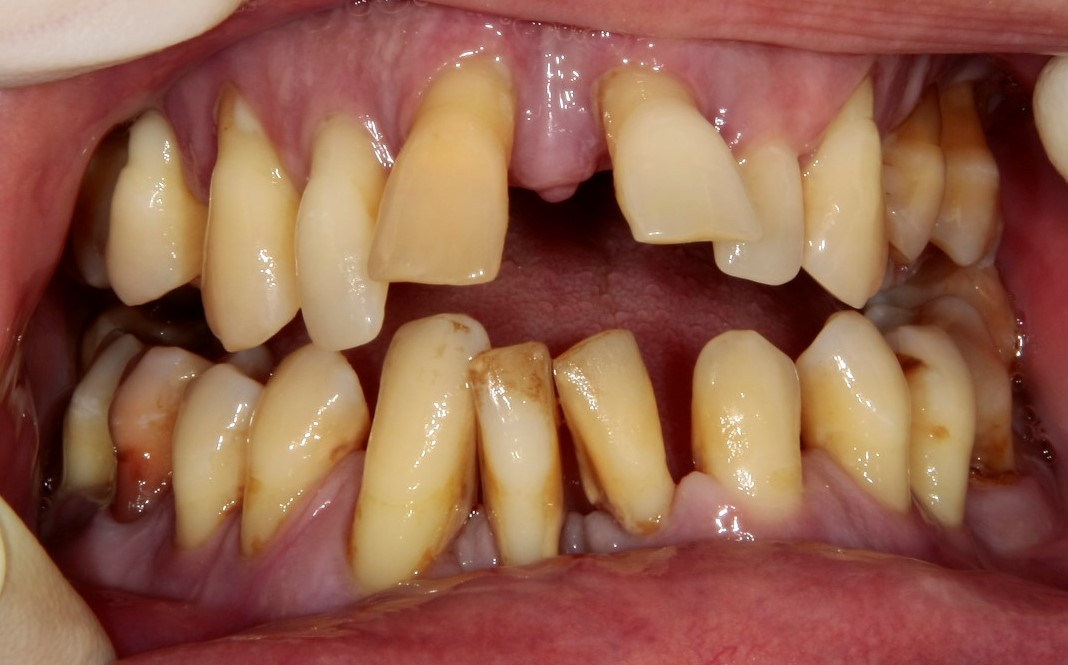

Это изначальная ситуация, та клиническая картина и те проблемы, с которыми вы приходите к доктору. И она может быть самой разнообразной, от полной катастрофы до вполне приемлемого состояния полости рта, когда требуется лишь профессиональная гигиена.

Как правило, проблемы с зубами не появляются мгновенно, а развиваются и накапливаются годами. До определенного момента, вы и ваш организм с ними справляется, а потом… приходит время обратиться к врачу.

Каким бы тяжелым ни было состояние вашей полости рта, чтобы бы ни происходило с вашими зубами — всегда помните, что всё можно исправить.